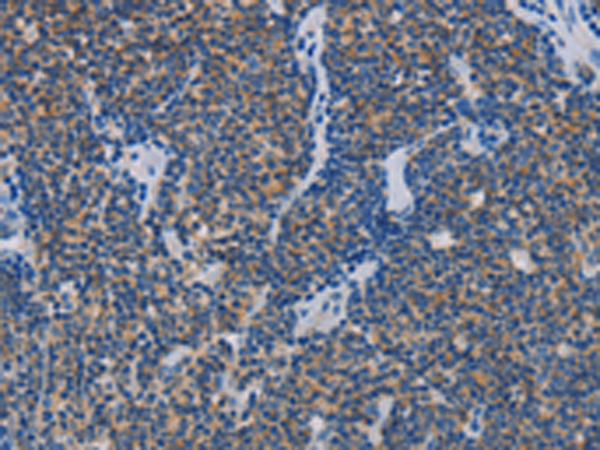

分类: 科研抗体货号: P07818别名: CDG1L; DIBD1; LOH11CR1J应用: IHC反应种属: Human, Mouse